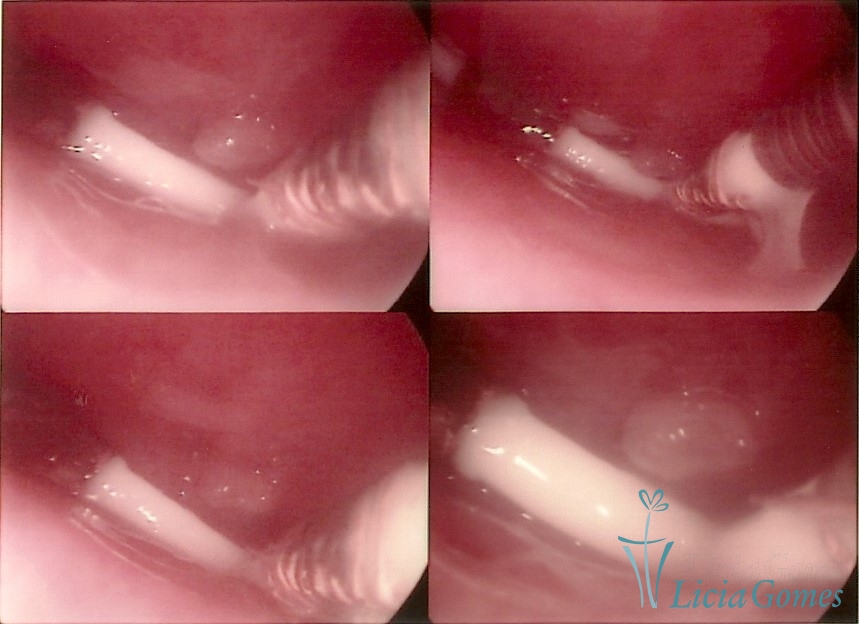

Cervical canal with IUD string